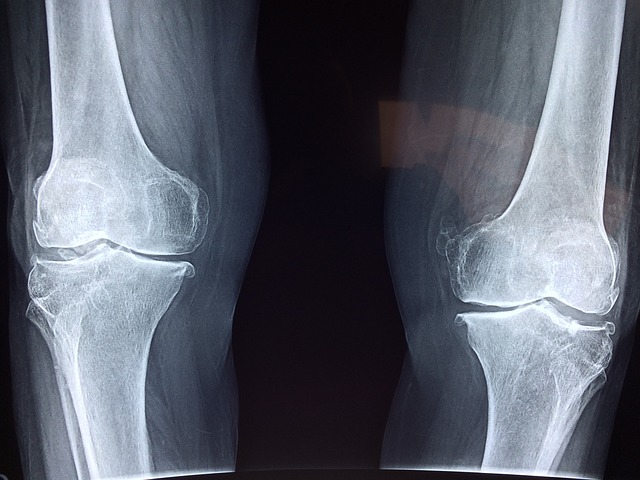

전문 치료는 언제 필요할까?

관절이 부어오르거나 극심한 통증이 지속되면 전문의를 찾아 정확한 진단을 받는 것이 중요합니다.

조기 치료는 퇴행성 관절염 등 심각한 질환으로 진행되는 것을 막아줍니다.